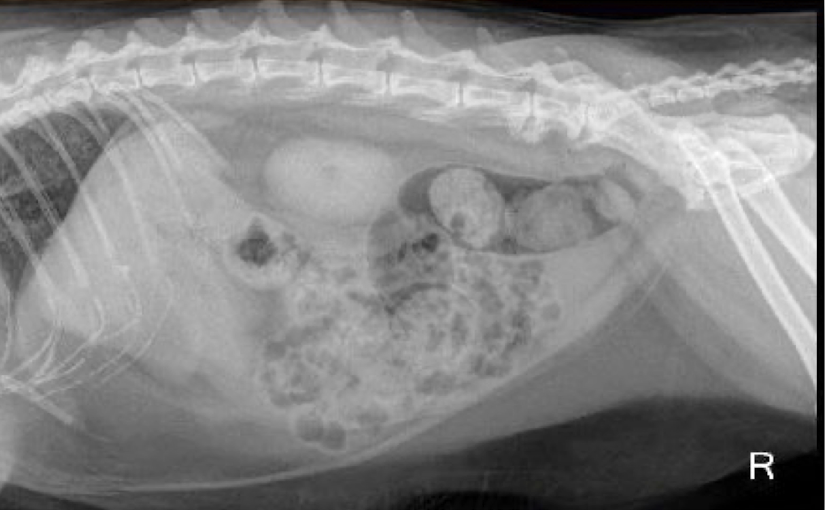

What is this animal most likely suffering from?

constipation